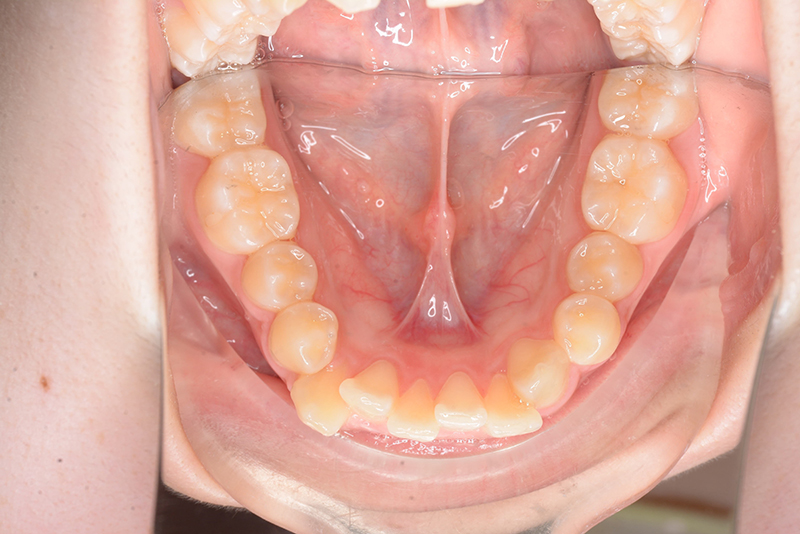

| 口腔内所見 | over jet 3.8mm、over bite 30mm、臼歯関係I級、上下顎前歯部に叢生が認められ、下顎正中は右側へ4.5mm偏位していた。左上5はCRの治療痕が認められた。 |

| パノラマ所見 | 上顎両側第三大臼歯は欠損、下顎第三大臼歯は埋伏していた。 |

| 批評・予后 | 治療後において閉唇時の頤筋の過緊張の改善及び咬合の緊密化と歯根のパラレリングが認められ、良好な咬合が確立できたと思う。 現在は保定をしつつ下顎両側第三大臼歯抜歯の抜歯を検討している。 |